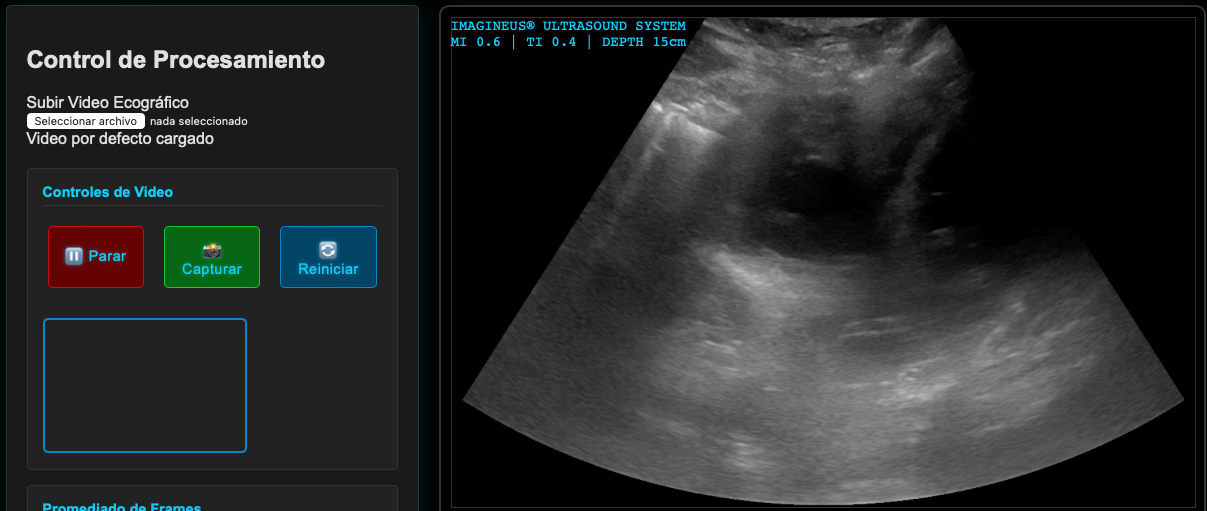

👉 Pulsa sobre la imagen para acceder.

Interacción Sonido con tejidos: Just do It!

Figura 6: Accede a Imagine Ultrasound Y Cambia de Sonda]

Los sistemas de ultrasonido modernos optimizan continuamente y automáticamente la imagen mientras se escanea. Sin embargo, algunos parámetros pueden ser ajustados por el usuario para optimizar aún más la imagen:

Demostración Interactiva: Ajuste de Parámetros de Ultrasonido

De la Señal a la Imagen

La conversión de la señal de ultrasonido en imágenes implica el uso de algoritmos sofisticados que interpretan los ecos y generan representaciones visuales.